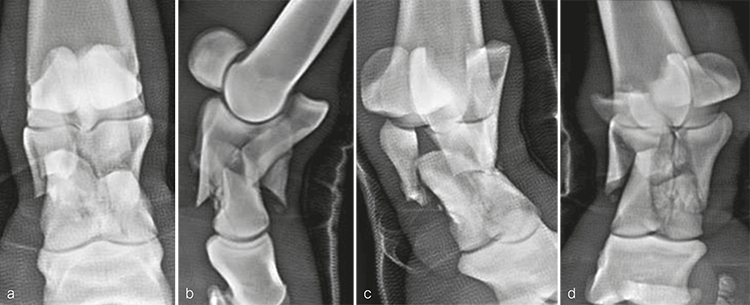

Radiographic evaluation at the time of admission confirmed the highly comminuted fracture configuration and revealed considerable collapse of P1 with malalignment and overriding of the fracture fragments (Fig 3). Due to the highly unstable nature of the injury and the presence of multiple sharp fracture fragments, the immediate concern was the potential for skin penetration and conversion to an open fracture. Consequently, the mare was placed under general anesthesia to facilitate indirect fracture reduction through traction on the distal limb. Once alignment was confirmed radiographically, the distal limb was stabilized by application of a fiberglass cast extending distally from the proximal metacarpus and incorporating the hoof.

A 10-year-old French warmblood gelding weighing 580 kg was presented a few hours after developing a severe left forelimb lameness following an unwitnessed paddock injury. Initial radiographs demonstrated a severely comminuted, minimally displaced fracture of P1 (Fig 7). The distal limb was immediately placed in a fiberglass cast by the referring veterinarian before transporting the horse, which prevented further displacement of the fragments.